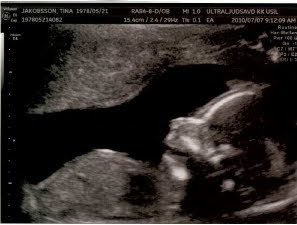

Varit och tittat på bebisen idag

Idag har vi varit på ultraljud och tittat på bebisen i magen. Allt var bra med den, den såg till att både vinka och skratta lite åt oss där den ligger i profil på bilderna.

Precis som dess mamma hade den växt på bra, så det beräknade datumet för födseln tidigarelades lite, nu beräknat till den 28 november.